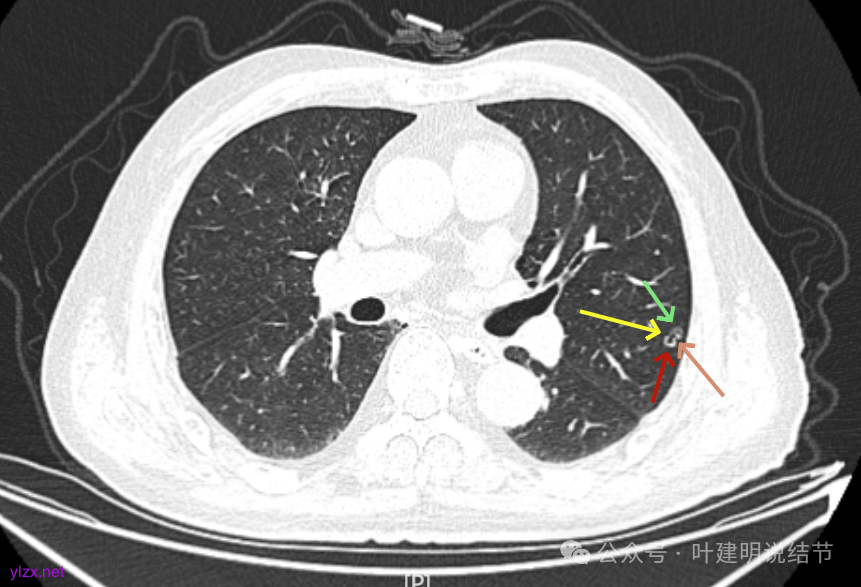

先来看2025年1月的影像:

有囊腔,表面不平,部分囊壁是磨玻璃成分。

病灶囊壁稍不均,多密度较高,表面欠平。

病灶整体的囊壁稍不均,靠内侧有磨玻璃成分。

囊壁不厚但密度较高。

囊腔内壁稍显不光滑,有少许突起于囊腔内。

上图也见囊腔内壁有突起,此层囊壁大部分呈磨玻璃密度。

边缘区是淡磨,内壁少许突起。

左肺上叶红色这处是囊腔型病灶,囊壁略不均,似有微小血管进入囊壁,对比2023年4月整个囊腔来讲有扩大,需要考虑囊腔型肺癌的可能性大。右侧蓝色的并不是典型囊腔型肺癌的表现,再加上两肺绿色这些慢支肺气肿与肺大泡的影像,右侧的就更加不确切,至少近期不能够考虑右侧也要开刀的事情。其实左侧的主病灶相对于其他表现更典型的囊腔型肺癌来说,由于囊壁密度偏高,也不是百分百必定是肺癌。我的想法还是先等脑梗情况稳定,并且间隔4~6个月复查病灶再有进展在考虑单孔胸腔镜下局部切除就可以。淋巴结可以考虑采样,但一般不至于阳性。破是不会切破的。消融不建议,囊腔灶更难通过穿刺获得病理依据,况且东西在边上,能局部楔切,当然首选手术。意见供参考!